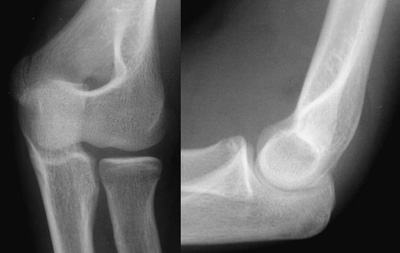

Step 5: Radio-capitellar line

This line is drawn through the middle of the radius posteriorly/rostrally and should bisect the capitellum on both the lateral and the AP elbow radiograph. Failure to align properly indicates a radial head dislocation that requires prompt reduction if neuro-vascular compromise is to be avoided.

Normal radio-capitellar lines